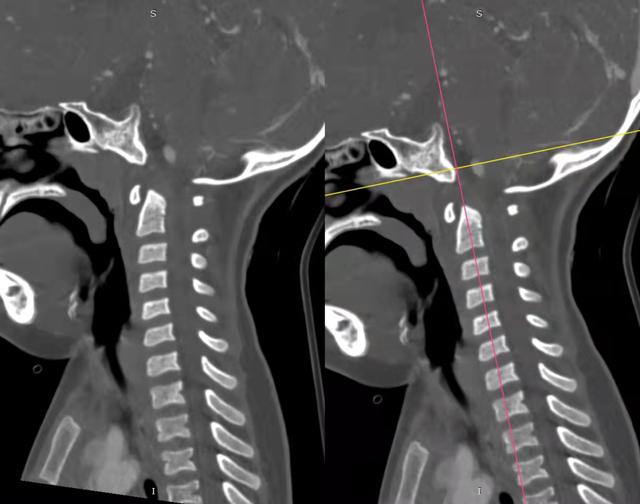

al-align:top;”> 孩子,望你早日康复! 这是一个关于 2岁宝贝的故事 为何这个幼儿平地摔倒,外表毫无受伤痕迹,却出现全身瘫痪,甚至呼吸功能衰竭? …… 为何凌晨时分,重医一院急诊科传来了救护车急促的汽笛声? …… 病史 患儿女,2岁零11个月; 于家中玩耍时平地跌倒致短暂意识丧失,苏醒后四肢瘫痪,自主呼吸微弱,病情危急! 为什么? 影像 患儿在当地医院作了急诊CT检查,发现…… CT显示:寰枢关节不稳 MRI:患儿呼吸不好,病情已不允许作了 分析 1. 尽管没有MRI检查,但根据CT显示的寰枢椎不稳,结合患儿四肢瘫痪,自主呼吸微弱的症状,颈延髓损伤明确; 2. 临床诊断:1)寰枢椎脱位 2)颈延髓损伤 怎么办? 方案 刻不容缓,做急诊手术准备! 寰枢关节不稳必须立即解决,否则有延髓再损伤的风险! 急诊手术:“寰枢椎复位+颈1-2融合内固定术+后路寰枕减压” 难点 患儿年龄小且发育较差,身高较同龄幼儿少10cm,体重仅仅11kg,上颈椎手术本就属脊柱高危手术之一,而幼儿的上颈椎骨质细小,在幼儿的上颈椎进行内固定手术,更是难上加难; 经验 重庆医科大学附属第一医院虽然是一所主要面向成人的综合性医院,但本院神经外科脊柱亚专业组,在幼儿脊柱手术方面具有丰富经验,尤其是对幼儿上颈椎损伤、颅底凹陷、先天性颅颈畸形、寰枢椎脱位等疾病,手术技术娴熟,成功完成过从2岁至13岁不同年龄幼儿的上颈椎手术。 既往病例文章分享: # 从13岁到2岁 # 一例“复杂”幼儿颅颈畸形 # 挑战幼儿 —— 3岁11月颅颈畸形手术病例分享 # 病例分享 || 幼儿复杂颅颈畸形 ……………… 本例患儿的手术在入院后2小时立即进行,并成功完成。解决了患儿寰枢椎不稳的风险,为其后续治疗的安全性提供了强有力的保障。 术后情况 术后CT示寰枢椎完美复位,寰枕区减压充分, 避免了患儿颈延髓神经功能二次损伤可能,为康复争取时间! 小宝贝术后虽然颈椎稳定了, 也减压了。 但是一时还无法脱离呼吸机, 也无法离开监护室, 无法见到自己爸爸妈妈! 不要害怕,宝贝! 重医一院神经外科脊柱亚专业组 和神经重症亚专业组的叔叔阿姨们 以及神经外科的护士小姐姐们, 会一直守护在你身边, 为你保驾护航! 宝贝加油! 相信你一定能战胜病魔,茁壮成长! 老晏说 幼儿脊柱疾病,亦在重庆医科大学附一院神经外科!